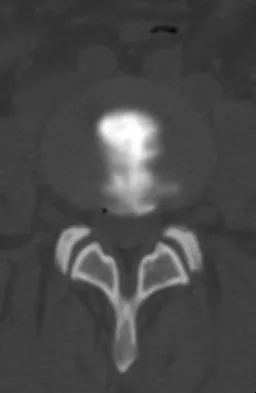

Which of the following findings best describes the acetabular fracture shown in Figure 38?

Explanation

The CT scan shows a posterior wall fracture with impaction of the articular surface and a free fragment within the joint. Proper treatment of this injury requires not only reduction and fixation of the posterior wall fragment but also removal of the free fragment and elevation of the depressed articular segment. Letournel E, Judet R: Fractures of the Acetabulum, ed 2. Berlin, Germany, Springer Verlag, 1993.